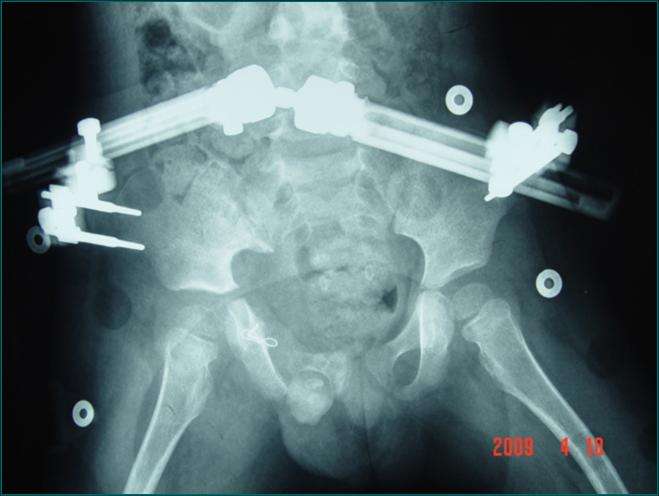

骨盆粉碎性骨折

骨盆粉碎性骨折,跟骨粉碎性骨折

骨盆粉碎性骨折 治疗

骨一科骨盆粉碎性骨折患者手术纪实